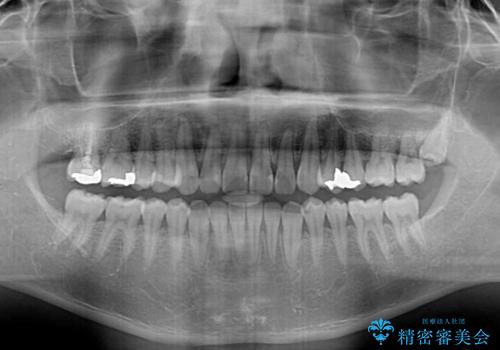

インビザライン・ライトは、製作できるアライナーの枚数に制限があるため、移動可能な量に限りがあります。

一方で、半年から1年程度で治療を終えることができるため、軽度の歯列不正の患者様には大変お勧めです。